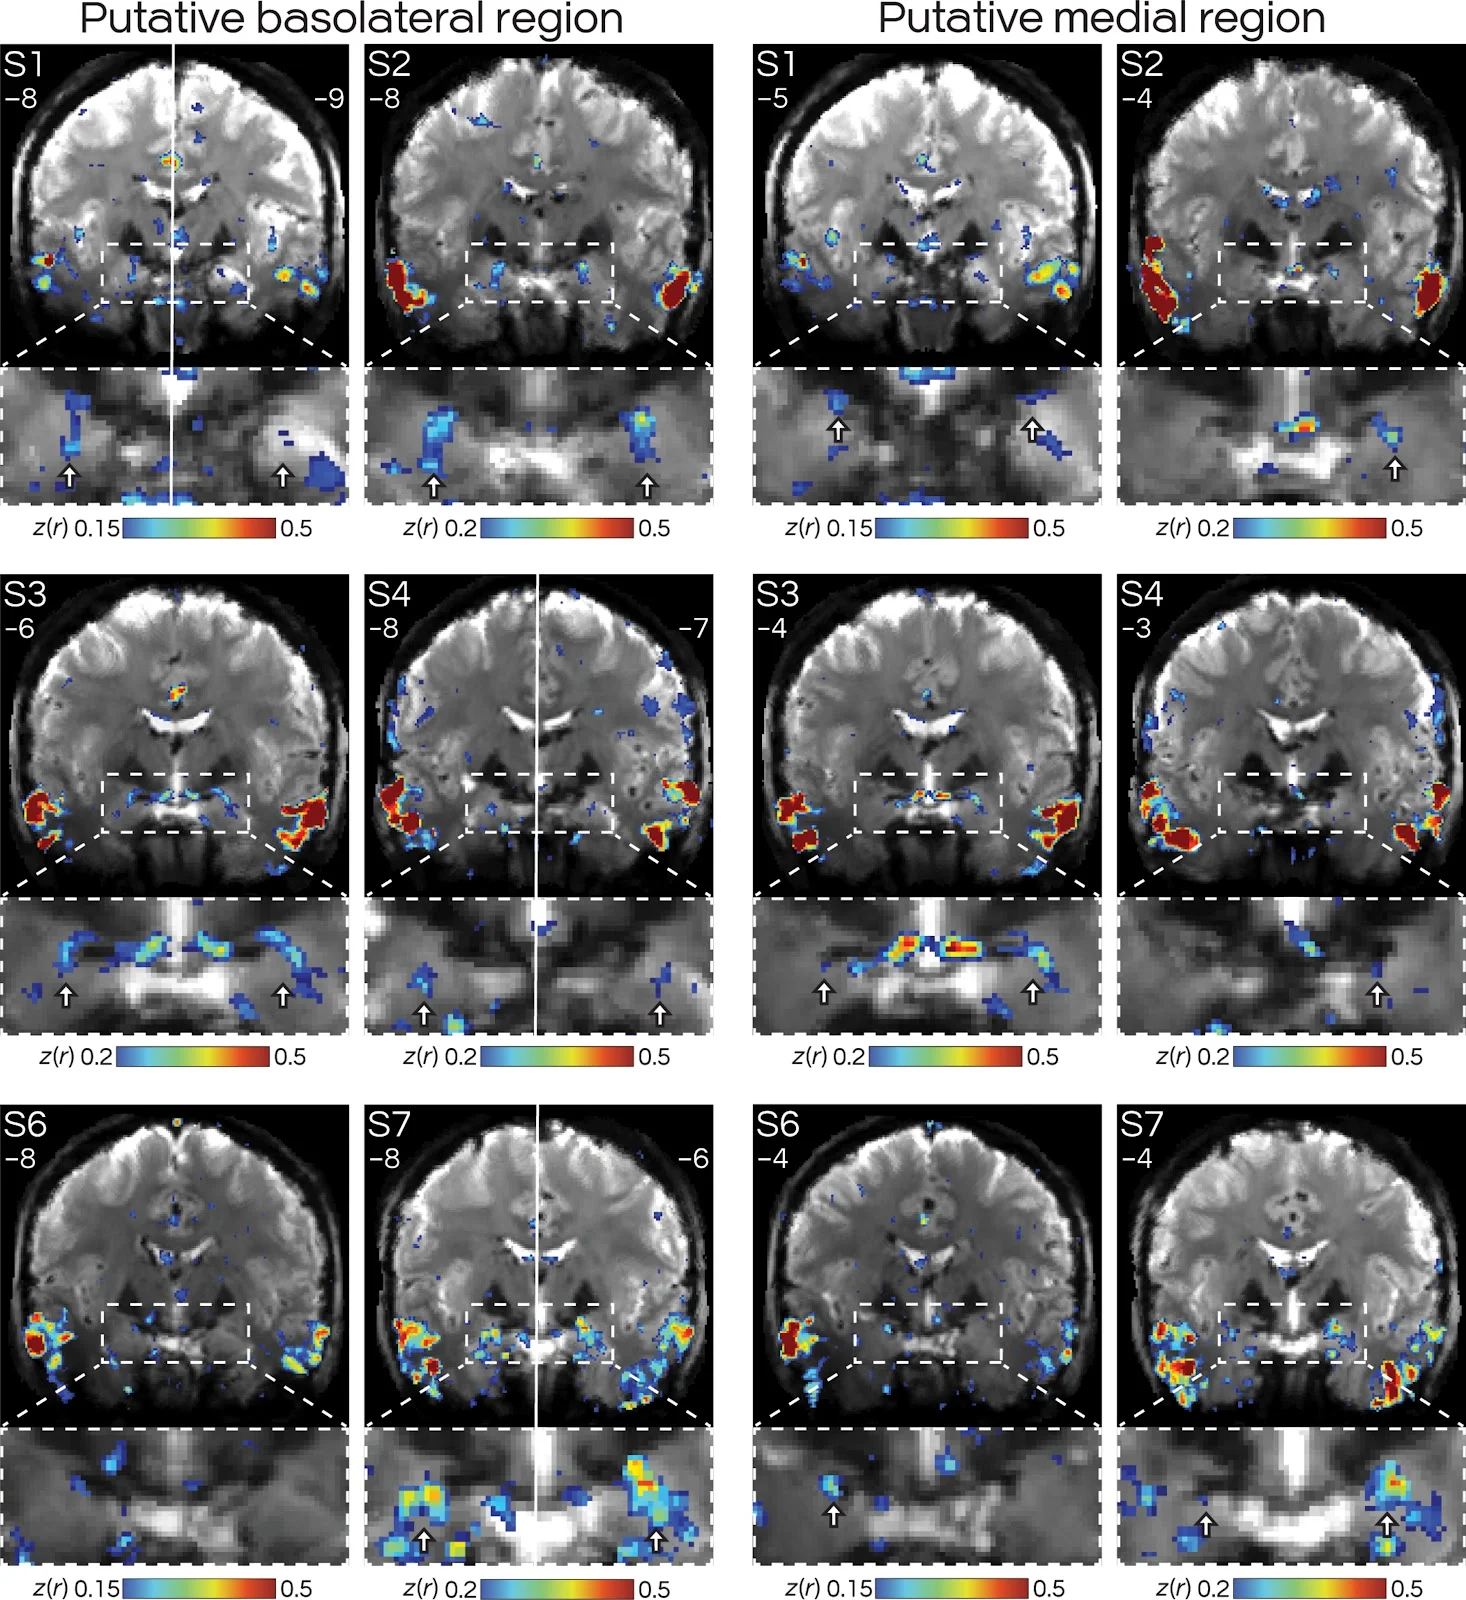

Fig. 4. Basolateral and medial amygdala regions of DN-B are bilateral and replicate across participants.

Volume-based FC maps of DN-B are shown in coronal slices. Numbers refer to the MNI coordinate of each slice. (Left) Views around y = −6 to −9, where five of six subjects (exception: S6) displayed bilateral regions putatively in the basolateral amygdala. (Right) Slices around y = −3 to −5, where, in all six subjects, a distinct set of bilateral (three of six) or unilateral (three of six) regions could be seen putatively near the medial amygdala (Fig. 6). The white solid line in S1, S4, and S7 denotes that left and right hemispheres are from different slices. Arrows denote putative DN-B regions that were distinct from DN-A (see Figs. 5 and 6 for overlap map at these same slices and replications in figs. S6 and S7).